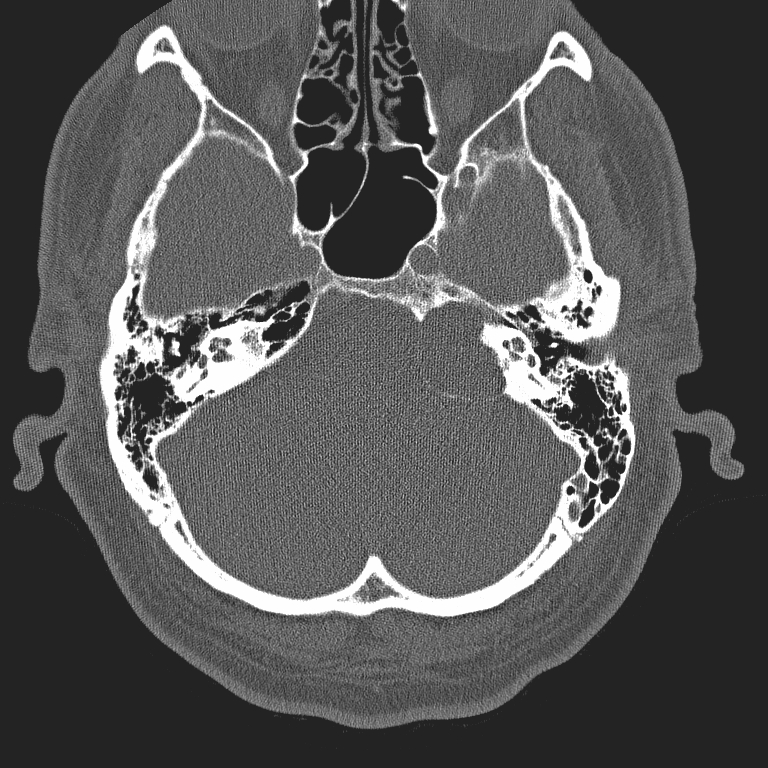

High-resolution CT (HRCT) is primarily performed at submillimeter intervals, and excels in the evaluation of bone and air space anatomy, and in disorders of the temporal bone, hearing ossicles and air cells. However, its role is limited in soft tissue pathology, mucosal thickening and fluid accumulation. In abnormalities of the middle ear HRCT is superior to MRI in most cases (except in tumours). HRCT is the modality of choice in conductive hearing loss, otoslerosis, and malignant otitis externa in diabetic patients and in surgery planning. One of the disadvantages of HRCT – especially in children - is the relatively high radiation dose to which the eye lenses are sensitive. Differentiation between hypodens structures filling the ear and air cells also might be problematic. HRCT’s role is also limited in the early detection of intracranial complications. Intravenous contrast administration in HRCT is not possible due to technical diffculties.

1. image: Patient with sensorineural hearing loss and tinnitus. MR-study (T2, precontrast T1 and postcontrast T1) reveal a mass in the left pontocerebellar angle without significant contrast enhancement. HRCT proves that the mass arises from the petrous pyramid, suggesting cholesterol granuloma. (Asklepios Klinik Altona, Hamburg)